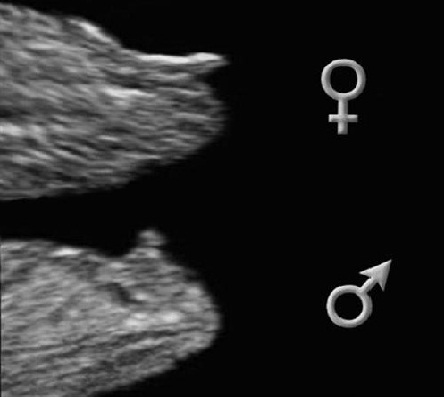

Полезла дома в инет, нашла такую картинку различий